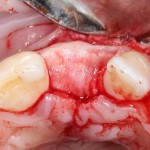

В этом случае остеопластика делается отдельной процедурой. Ее принципы точно те же, но уже без импланта. Например:

Имплантировать в таких условиях — заведомо обрекать себя на хреновый, с точки зрения эстетики и функциональности, результат. Поэтому первым этапом проводим остеопластику. Объем небольшой, использовать в таких объемах костный блок не очень рационально. Воспользуемся аутокостной стружкой и мембраной.

Сначала фиксируется BioGide. Это легко:

Затем укладывается и конфигурируется аутокостная стружка: